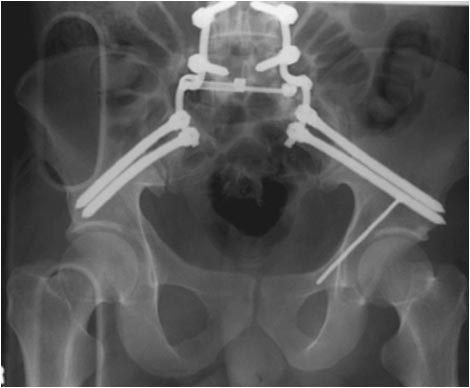

Доброго времени суток коллеги! Прошу вас подсказать тактику в решении оперативного лечения следующего сложного повреждения таза. Был ли опыт в фиксации подобных повреждений? Травма 03.12.2013,больная переведена из лечебного учреждения соседней области.На данный момент у больной следующий диагноз: ЗЧМТ,сотрясение головного мозга;Закр. травма грудной клетки,множественные переломы ребер справа с повреждением ткани легкого,правосторонний гемопневмоторакс,состояние после торакоцентеза;Закр.травма живота,разрыв селезенки,гемоперионеум, состояние после лапаротомиии спленэктомии;Закр. оскольчатый перелом сред-верх\3 левой бедренной кости, состояние после накостного металлостеосинтеза; Закр.поперечный переломовывих на уровне S1S2, многооскольчатый перелом латеральных масс крестца с обеих сторон,перелом обеих лонных и седалищных костей. Перелом поперечных отростков L1,L2,L3,L4, L5 позвонка. ШОК 3ст. Вкратце изложил диагноз. В настоящее время состояние больной тяжелое. Первым этапом планируем наложить АНФ (переднюю раму) После стабилизации состояния необходимо будет выполнить фиксацию: . Имеется один вопрос - какие импланты необходимы т.е. в какой комбинации и какая последовательность фиксации?

Вам надо начинать сзади. Пример в файле.

Добрый день! Станислав! Повреждение таза действительно тяжелое. В данном случае по мимо перелома передних колонн, что не самое страшное, имеется H-образный перелом крестца со смещением каудальной части. перелом поперечных отростков подтверждает вертикально нестабильный характер травмы таза. Предложенная конструкция действительно является вариантом решения проблемы,а скомпоновать ее можно из любого транспедикулярного фиксатора той фирмы которая работает у вас с нейрохирургами.Но помимо этого необходимо выполнить декомпрессию корешков конского хвоста. в противном случае та неврология которая есть и сейчас останется на всю жизнь. Судя по тяжести состояния к лечению перелома крестца сможете приступить не скоро, скорее всего на данный момент доминирует легочный дисстресс синдром, наверняка есть анемия после гемопневмоторакса, лапаротомии и накостного остеосинтеза бедренной кости.Поэтому когда дойдет дело до крестца репонировать отломки будет весьма сложно. Мы бы начали с остеосинтеза ребер, чтобы сделать пациента мобильным, передние колонны можно фиксировать перкутанно винтами, сзади кроме илиолюмбальной конструкции, ляминэктомия с целью декомпрессии, репозиция и дополнительная фиксация реконструктивными пластинами, лучше LCP. Пригласите на операцию нейрохирурга-вертебролога. Успехов.

Для фиксации крестца предложены различные методы и представленный снимок является одним из примеров. Если местные возможности позволяют, и имеются специалисты, знающие методы, которые помогут создать эстетичную фиксацию, надо этим воспользоваться. Но ради красивой картины не стоит жертвовать неизвестной для вас методикой.

В данном случае кроме фиксации крестца требуется декомпрессия канала. А вправленный вывих надо удержать, и вертикальные пластины с юникортикальной возможностью в 2.7 мм помогут создать стабильность. Кроме этого, надо создать условия по предупреждению компрессии крестца с двух сторон. В связи с тем, что процедура заканчивается в области крестца, а также наличие повреждения позвонков, это ограничивает возможности педикулярной фиксации. Мне кажется, от боковой компрессии лучше удержала бы согнутая по контуру крыла узкая в 4.5 мм балка-пластина.

Отсутствие нижней элегантной наружной фиксации минус, но не менее популярный в ваших краях фиксатор из частей аппарата Илизарова также не уступает в жесткости. Несмотря на неудобства, фиксацию надо закончить дополнительной передней наружной рамой.